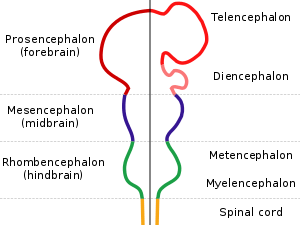

The diencephalon is part of the prosencephalon (forebrain), which develops from the foremost primary cerebral vesicle. The prosencephalon differentiates into a caudal diencephalon and rostral telencephalon. The cerebral hemispheres develop from the sides of the telencephalon, each containing a lateral ventricle. The diencephalon consists of structures that are lateral to the third ventricle, and includes the thalamus, the hypothalamus, the epithalamus and the subthalamus.

Diagram depicting the main subdivisions of the embryonic vertebrate brain. These regions will later differentiate into forebrain, midbrain and hindbrain structures.